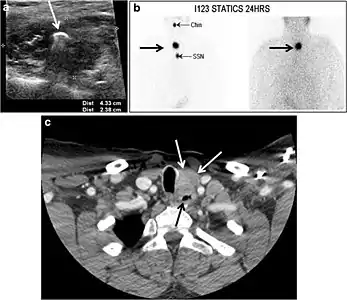

Fig. 22. A 26-year-old male patient with elevated serum parathyroid hormones and calcium secondary to intra-thyroid parathyroid adenoma. a, b Enhanced axial and coronal CT scan of the neck demonstrate a well-defined hypodense right thyroid nodule (white arrows). c Bone window coronal CT scan shows lytic expansile lesions at the right mandible and left frontal bone (white arrows). d Transverse colour Doppler ultrasound of the neck demonstrates a well-defined, heterogonous, predominantly hypoechoic right thyroid nodule measuring 2.7 cm, with mild increased vascularity and no internal micro-calcifications (white arrow). e, f Delayed anterior planar and fused SPECT/CT parathyroid Sestamibi scan at 2 hours demonstrate persistent focal activity in the right thyroid lobe (white arrows). Note the scattered mandibular/maxillary uptakes in planar image representing the known brown tumours.[1]